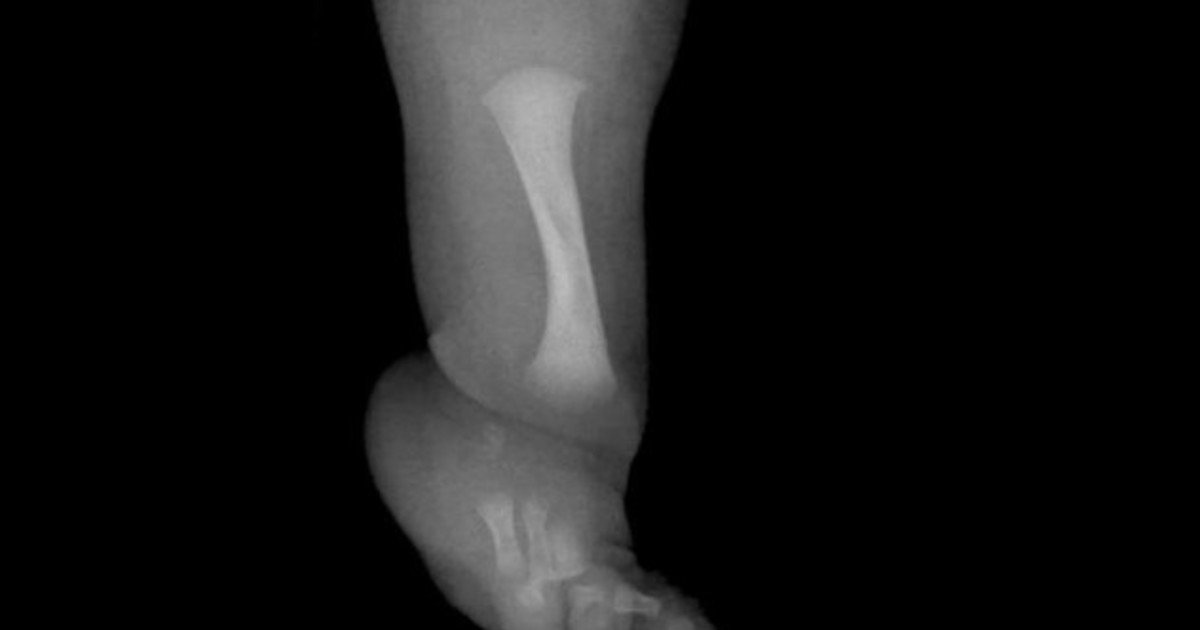

Noticias Un nene con una rara enfermedad fue operado para desarrollar un hueso fundamental Radio Brisas del Sur 18 de febrero de 2026 1 minute read 0 Un niño de nueve años se ha sometido en el Reino Unido a una cirugía pionera. Es para menores que tengan hemimelia fibular. Acerca del autor Radio Brisas del Sur Administrator Visitar el sitio web Ver todas las entradas Navegación de entradas Anterior: Buenas noticias en Texas: Abbott anunció que NRG Energy invertirá 617 millones de dólares en nueva planta de gas en HoustonSiguiente: John Malkovich viene a la Argentina para hacer una sola función de una obra sobre la represión en tiempos de Pinochet Deja una respuesta Cancelar la respuestaTu dirección de correo electrónico no será publicada. Los campos obligatorios están marcados con *Comentario * Nombre * Correo electrónico * Web Guarda mi nombre, correo electrónico y web en este navegador para la próxima vez que comente. Noticias Relacionadas Noticias Clima hoy en Punta Lara, Buenos Aires: el pronóstico del tiempo para este domingo 15 marzo de 2026 Radio Brisas del Sur 15 de marzo de 2026 0 Noticias Daniil Medvedev dio el golpe del año en Indian Wells, le cortó el invicto a Carlos Alcaraz y jugará la final del Masters 1000 contra Sinner Radio Brisas del Sur 15 de marzo de 2026 0 Noticias Messi no viajó a Charlotte y el gol 900 deberá esperar: la explicación de Inter Miami a su ausencia en la MLS Radio Brisas del Sur 15 de marzo de 2026 0